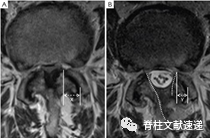

图注:术前(A)和最后随访(B)MRI对小关节保存的测量。虚线突出显示椎板切开的范围。小关节保存率=y/x×100%。

图注:对一例严重退行性腰椎管狭窄症患者行UBE减压术后的最终随访MRI(B)与术前MRI(A)对比显示,减压充分,硬膜横截面积和双侧小关节的保存改善明显。